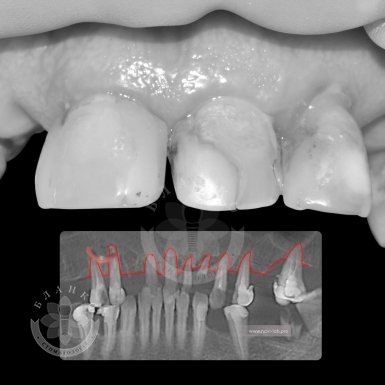

Зубная имплантация — это современное и надежное решение для восстановления утраченных зубов. В стоматологической клинике Бланко мы предлагаем имплантацию зубов «под ключ», что означает полный комплекс услуг — от диагностики до установки коронки, без скрытых платежей и неожиданных расходов.